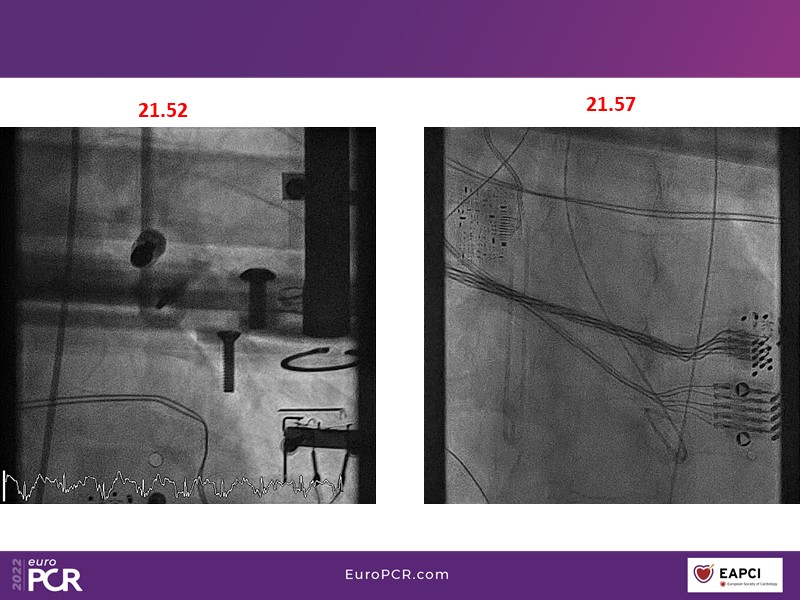

Tailored support for complex PCI and AMI with percutaneous mechanical circulatory support

Watch this EuroPCR 2022 session, in which Javier Escaned, Florim Cuculi, and Norman Mangner present different cases, to learn how standard operating procedures including mechanical circulatory support improve outcomes in patients with complex coronary lesions, discuss new strategies to overcome ischemic reperfusion lesions using percutaneous mechanical circulatory support, and understand the benefits of mechanical circulatory support in AMI patients.

- To discuss new strategies to overcome ischemic reperfusions injury by using percutaneous mechanical circulatory support